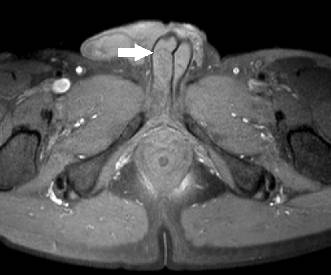

Bij patiënt Y was er sprake van een trombose van het linker corpus cavernosum. Op de echo was nog wel enige flow in het corpus zichtbaar, maar deze was duidelijk verminderd ten opzichte van de flow in het rechter corpus cavernosum. Op de MRI werd in beide gevallen een membraneuze structuur gezien, die het proximale en distale deel van het corpus cavernosum van elkaar scheidde (fig. 1).

Figuur 1

MRI-afbeelding van patiënt X. De pijl wijst naar het septum, dat het proximale deel van het corpus cavernosum scheidt van het distale deel.

De meest frequent beschreven risicofactoren die geassocieerd zijn met partiële trombose zijn: een trauma, fietsen/wielrennen, langdurige coïtus, lange vliegreizen, eerder priapisme, hematologische aandoeningen (zoals sikkelcelanemie), gebruik van PDE5-remmers en alfablokkers, en drugsgebruik. Toch lijkt het ontstaan meestal idiopathisch [111]. Wel verdient het aanbeveling om hematologische tests te verrichten of de patiënt voor dergelijke tests door te verwijzen naar de hematoloog. Weyne et al. beschrijven dat bij patiënten met een stollingsstoornis de aandoening vaker optreedt [1]. Een interessant gegeven is dat in veel gevallen op MRI-beelden een dunne membraan werd gezien in de corpora cavernosa bij patiënten met segmentaal priapisme, terwijl dit membraam ontbrak op MRI-beelden bij controlegroepen [6]. Het membraan scheidt het proximale deel van het corpus cavernosum van het distale deel [4]. Het ontstaan en de exacte rol van het membraan in de pathofysiologie is nog niet bekend. Er wordt gedacht dat een dergelijk septum kan ontstaan door microtraumata van het corpus cavernosum, bijvoorbeeld door wielrennen [4, 12, 13]. Een groter trauma zou daarna een partiële trombose kunnen uitlokken. De meningen hierover zijn echter verdeeld. Zo beschrijven Hulth et al. een patiënt bij wie het septum al zeven jaar voor de trombose op een MRI-scan ontdekt werd en bij wie geen groot trauma voorafging aan de trombose die uiteindelijk bij hem ontstond [6]. De twijfel wordt verder versterkt door de bevinding dat het septum altijd bilateraal aanwezig is, terwijl de trombus zich vaak aan één zijde bevindt [6]. Daarnaast treedt de aandoening vaak op bij jonge mannen [46, 14]. Indien een septum daadwerkelijk zou zijn ontstaan door recidiverende microtraumata en een trombose geluxeerd zou worden door een groter trauma, zou je de aandoening vaker verwachten bij oudere mannen. Daarnaast zou je verwachten dat een partiële trombose vaker bij fanatieke fietsers zou optreden [6].